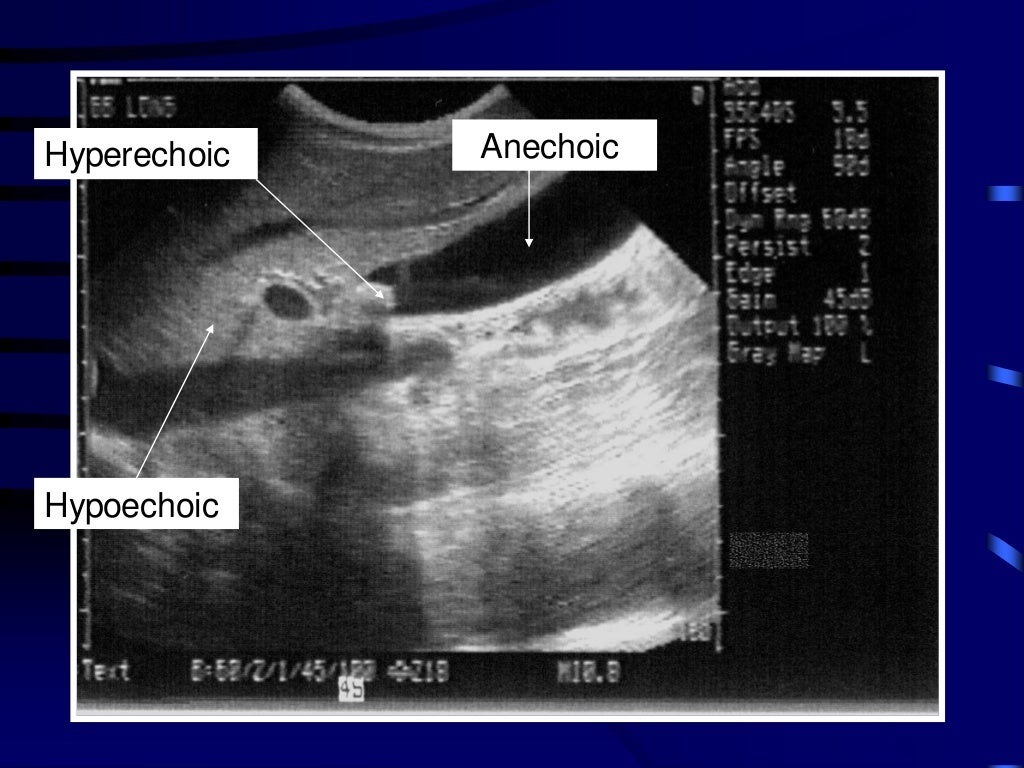

Examples of PE on the chest ultrasound. Anechoic space represents fluid... Download Scientific What Is A Chest Ultrasound A chest ultrasound is an imaging test that uses sound waves to look at the structures and organs in your chest. The thoracic anatomy is composed of the chest wall that is made of musculature including intercostal muscles and pectoralis. A chest ultrasound is an imaging test. It can help your healthcare. What is a chest ultrasound? It uses sound. What Is A Chest Ultrasound.